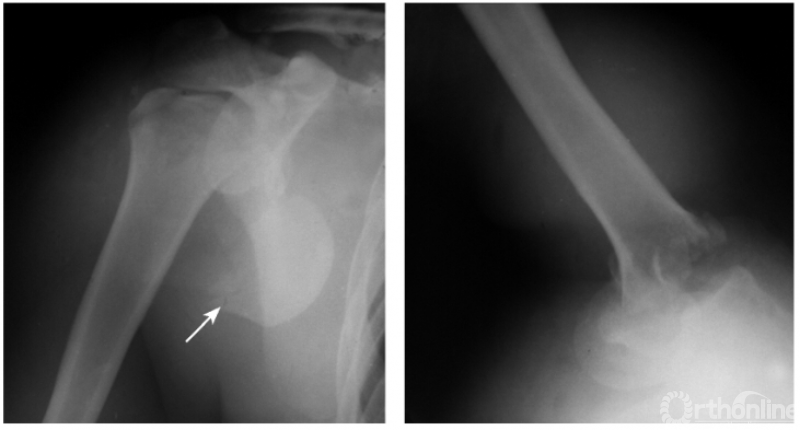

四、肩关节后脱位

肩关节后脱位是所有大关节脱位中最易误诊的一种损伤,其误诊率可高达60%,因此该病有“诊断的陷阱”之称,有学者指出肱骨头关节面与盂前缘距离大于6mm时应高度怀疑有后脱位的可能。

此外,由于脱位后上臂外旋受限,因此即使在最大外旋位拍片时仍不能显示出肱骨颈及大结节的轮廓。例:肱骨头离开关节盂而向后外上方(肩峰之下)移位且内旋,致肱骨头与肱骨干在一直线上,招致肩肱曲线不流畅,肱骨头关节面与盂前缘距离大于6mm并小结节骨折(如下图)。